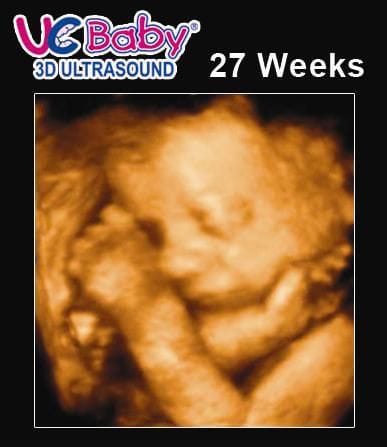

Pregnancy Week 27 3d Ultrasound

Pregnancy week 27 3d ultrasound. 27 weeks pregnant ultrasound inside your 27 weeks belly baby is practicing inhaling and exhaling with their rapidly developing lungs. Normal 25 week pregnancy and ultrasound the useful guide. Unfortunately thats not the only thing thats swelling. An ultrasound at 27 weeks will show a baby in various actions.

3dultrasound 27weekspregnant pregnantduringapandemic hey friends. Two weeks ago your belly was a soccer ball and by 27 weeks pregnant your uterus has swelled to the size of a basketball. Your list of pregnancy symptoms at 27 weeks includes. Week 27 ultrasound now that the baby to be is growing rapidly its harder to get a complete profile in the womb he just doesnt fit in the picture anymore.

Beginning somewhere around this stage of pregnancy nearly 3 in 4 pregnant women start to experience mild swelling of the extremities particularly the feet. 27 weeks pregnant ultrasound. Even though he has more than tripled. From here on out babys brain will keep getting more complex turning that 27 week fetus into a real smarty pants.